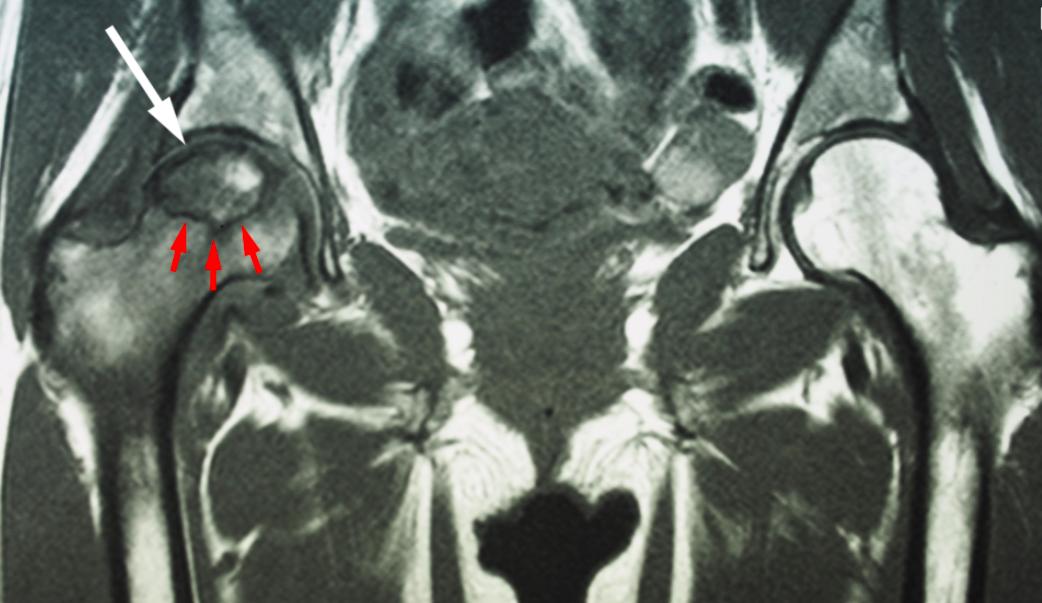

磁共振成像 (MRI) 扫描。 可以通过 MRI 扫描检测到 X 射线上可能未显示的骨骼早期变化。这些扫描用于评估有多少骨骼受到疾病的影响。MRI 也可能显示尚未引起症状的早期骨坏死(例如 - 可能发生在对侧髋关节的骨坏死)。

MRI 扫描显示患者右髋骨坏死(白色箭头)。黑线(红色箭头)表示死骨和活骨之间的边界。患者左侧髋关节正常